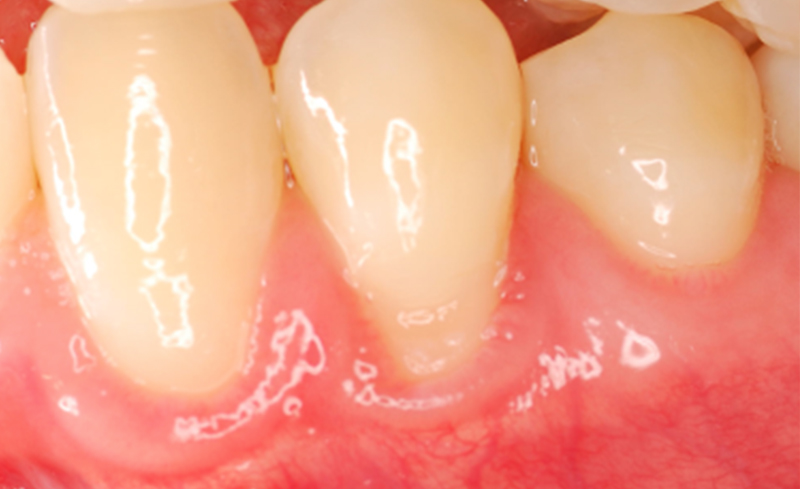

矯正治療後や慢性的な過度のブラッシング、歯周病などが原因で歯肉が痩せて歯根が露出することがあります。

歯根露出は審美的な問題、知覚過敏、歯根の虫歯の原因になります。この様なケースでは根面被覆術を推奨しています。根面被覆術では主に患者様ご自身の歯ぐきを露出した歯根面に移植します。

| 治療内容 | 初診時に左右下の臼歯部に歯肉の退縮が認められます(左二枚)。矯正治療が終了した1年後です。根面被覆術を行いました(右二枚)。 |

| 年齢 | 48歳女性 |

| 治療内容 | 初診時に左右上の前歯から臼歯部にかけて歯肉の退縮が認められます(左)。根面被覆術を行いました(右)。 |